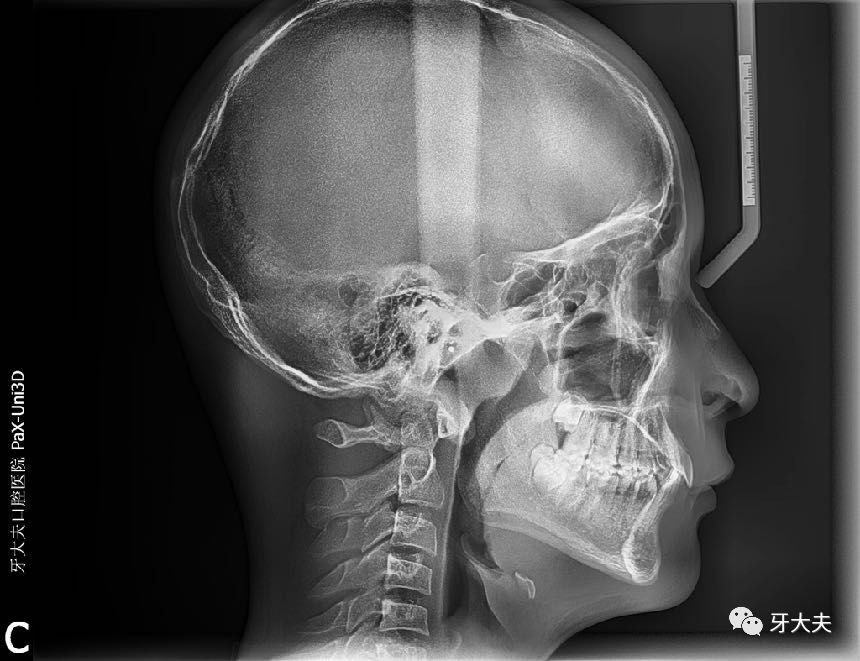

2016年10月23日侧脸照 2017年6月24日侧脸照

矫正牙齿也给我带来了非常积极的影响。以前常被同学取笑“没下巴”,自己也老是不自信。自从矫正了牙齿后,感觉自己笑得更欢乐,看上图对比照就知道了,另外高中的数理化感觉都变得简单了,大概是我不再因为牙齿不齐而自卑吧。